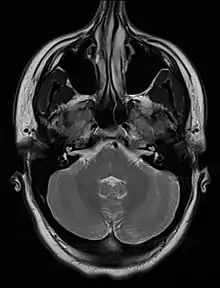

| An MRI image showing a congenitally deviated nasal septum, bowed to the left between the eye sockets | |